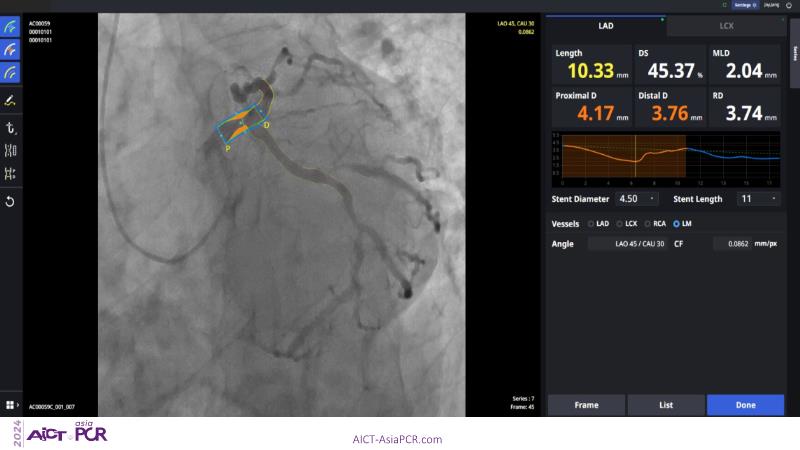

Exploring a recorded case of image-guided PCI of distal left main disease, as well as a new paradigm in AI-driven imaging, and learn how coronary imaging aids in decision-making, optimises final outcomes, and enhances stent clarity to guide results in complex PCI procedures. Watch now to deepen your knowledge of advanced imaging techniques for better procedural success.

- To learn how imaging can help in optimising final results

- To learn how stent clarity can be used to further guide final results